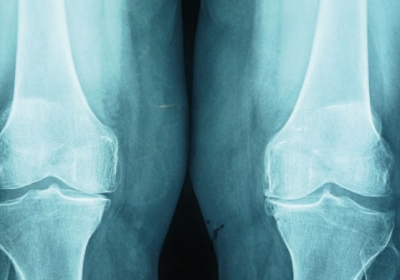

PTR con sustitucion de la rotula